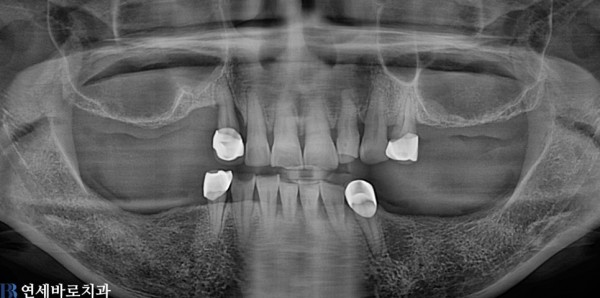

양쪽 어금니가 빠진후 방치한 채로 생활하시다 불편함을 느껴서 내원하신 환자입니다.

빠진 치아를 방치하게 된다면 잇몸뼈가 천천히 소실되어 임플란트를 심을 뼈가 부족하게 됩니다.

촬영시기: 22.08.10(전), 23.07.20(후)